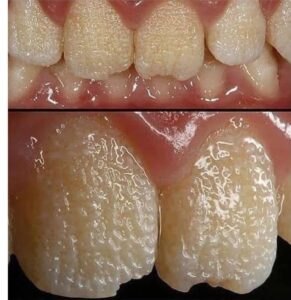

Problemas en la maduración del esmalte: El esmalte puede formarse con una textura rugosa o blanda, lo que aumenta su desgaste con el tiempo.